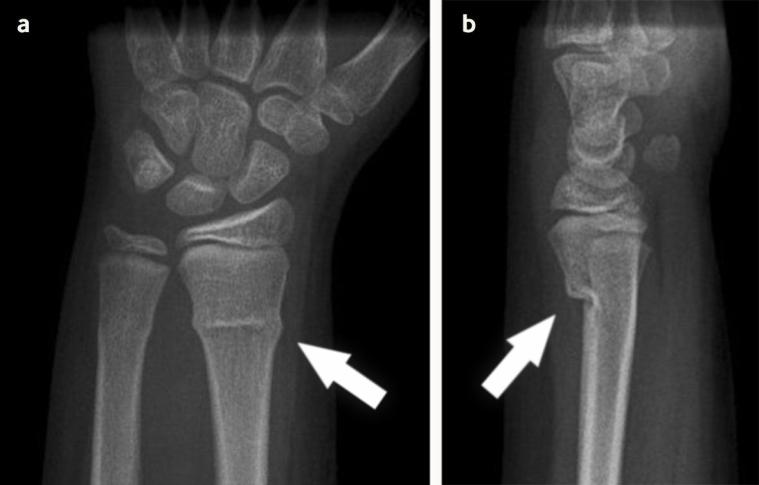

Buckle fractures, also known as torus fractures, are common injuries in children due to the flexibility of their bones. This type of fracture occurs when one side of the bone bends, raising a little buckle, without breaking the other side. It typically happens in the wrist when a child falls on an outstretched hand.